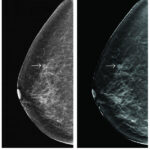

Mamografías: son imágenes de rayos X que detectan zonas anómalas en la mama. No tienen un 100% de fiabilidad por lo que pueden dar

Figura 2. Mastografía con inicio de cáncer

imágenes sospechosas que finalmente no sean malignas (falsos positivos) o dejar de diagnosticar algún tumor maligno (falsos negativos).